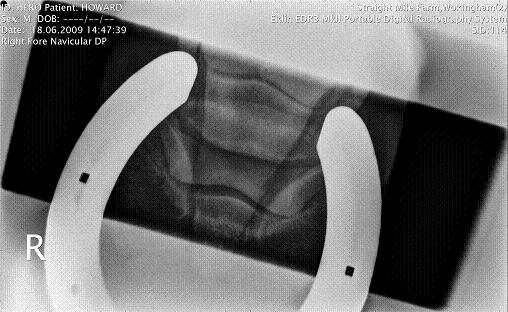

RF DP

RF Navicular DP

Radiographic findings:

"changes on ventral border of navicular bone within normal limits. slight erosion of toes right fore..small OSC chip left hind."

"foot balance synDrOme producing pedal bone compression"

Vet has recommended, bute, navilox, for 3+months plus natrual balance shoeing. No jumping.